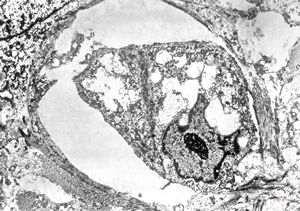

F,31y. | ovary - mucinous carcinoma